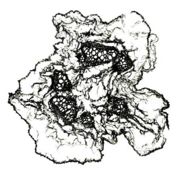

内部形態の比較(市場品)

浙江省産市場品の横切面では、形成層は明瞭で環状につながっている。道管は形成層の近くに散在しており、中央に髄がある。コルク層を表面視するとコルク細胞は厚膜の長条形である。 韓国産市場品の横切面では、維管束が放射状に配列し、形成層は不明瞭で放射組織によって分断され、環状につながらない。コルク層を表面視すると、コルク細胞は薄膜の多角形である。

韓国産の延胡索ではでんぷん粒が認められたが、中国産の延胡索ではでんぷん粒は認められなかった。これは、韓国産は生干しであるため、デンプン粒がつぶれずに認められるのに対して、中国産では湯通し加工の過程で、でんぷんが糊化しているためだと、考えられる(糊化したでんぷんは、偏光下でも光らない)。

| ○糊化でんぷん <中国産> |

○でんぷん粒 <韓国産> |